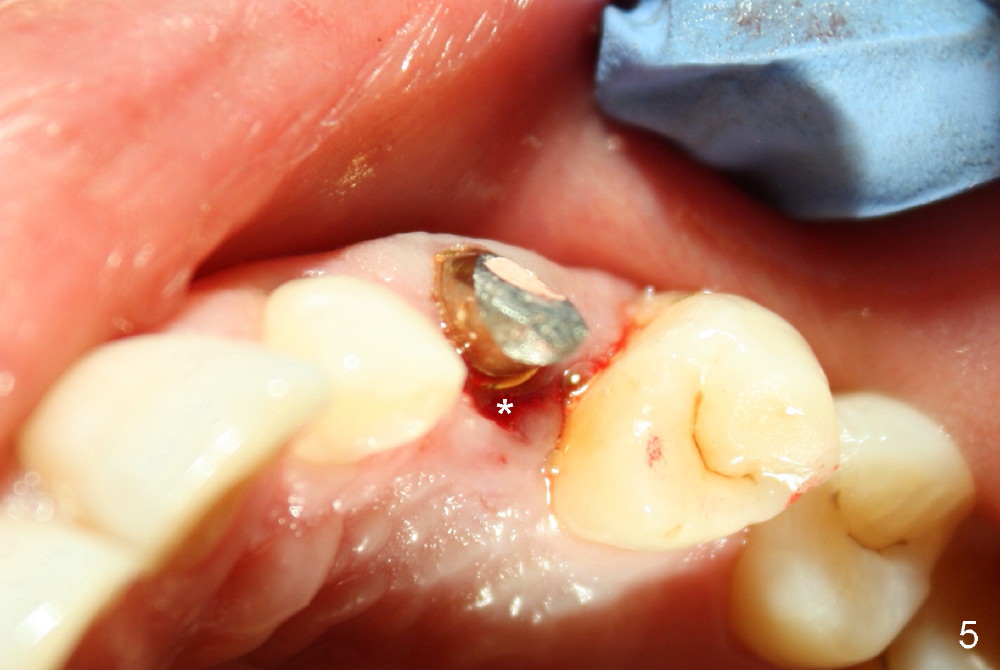

The 42-year-old lady refuses to take antibiotic prior to surgery due to lactation. The extraction of the upper left deciduous canine is not difficult as expected. There appears to be no granulation tissue. What is unexpected is difficulty in osteotomy. Initial osteotomy is too palatal, apparently perforating the palatal plate. The osteotomy has to be changed: slightly palatal to the center of the original socket (Fig.1: 2 mm pilot drill). As drills increase in diameter, the coronal end of the drills have to be tilted buccally, because it feels like that the labial plate at the apical end is going to be perforated. When 4.5x14 mm bone level implant is placed, the implant is sticking out too much (Fig.2). To alleviate this cosmetic issue, the implant is placed deeper (Fig.3). A 25º angled abutment is placed with heavy labial reduction (Fig.4,5). The patient is pleased with a stable new tooth, but the operator is not (Fig.6). Removal of the implant may be not the wildest guess. Two or three days postop, the patient reports pain and swelling. The symptoms disappears after antibiotic. One week follow up reveals wound healing normal. The gingiva returns to its normal color, as compared to purplish appearance in Fig.4,6 (immediately postop). In fact, the implant fails in a month.